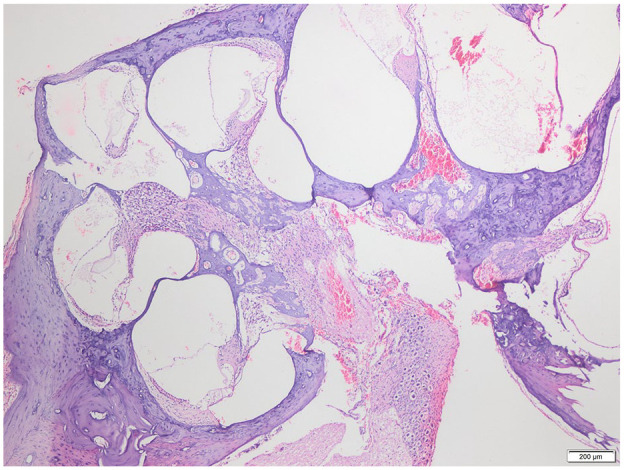

Objective: Despite vaccination and early antibiotic treatment, pneumococcal meningitis remains a disease with significant mortality and morbidity. The resulting inflammatory response can lead to cochlear fibrosis, ossification where cochlear implant surgeries are far challenging. Our study aimed to investigate the preventive effect of controlled-release dexamethasone implant in such cases in terms of structural integrity.

Methods: Twenty-four rats were induced with pneumococcal meningitis and randomized into study (n = 16) and control (n = 8) groups. Controlled-release dexamethasone implants were placed transbullarly into the right round window of the study group. Bilateral cochleas underwent histological examination 3 months post-infection.

Results: In the study, cochlear effects of pneumococcal meningitis were evaluated. The basal turn was significantly more affected by fibrosis and ossification (P = .013 and .010, respectively). Compared with control ears, the dexamethasone implant group showed less fibrosis in all turns and less ossification in the basal turn (P = .014, .003, .044, and .035, respectively).

Conclusion: In pneumococcal meningitis, fibrosis and ossification occur more intensively in the basal turn of the cochlea. Controlled-release dexamethasone implants are effective in preventing cochlear ossification and fibrosis. The prevention from the structural damage indicates the potential role of these dexamethasone implants in post-meningitic hearing loss and easing cochlear implant surgeries.